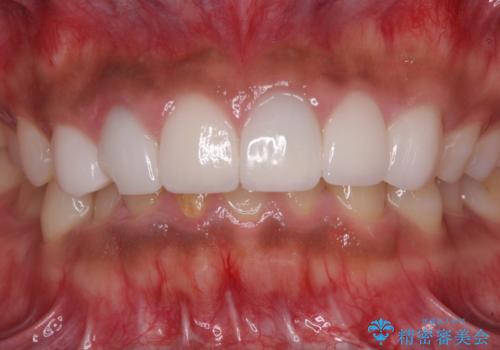

欠けてしまった前歯のセラミック 同じ色合いで再製作

- 前歯のセラミッククラウンが欠けてしまったとのことで来院された患者様です。

周りの他の歯もセラミッククラウンやラミネートベニアが装着されていたため、欠けてしまったクラウンを丁寧に取り外し、同じような色合いとなるように製作することとしました。

欠けたセラミッククラウンを丁寧に外して技工所に送ったことで、元のセラミッククラウン同様の色合いとなり、自然な仕上がりとなりました。